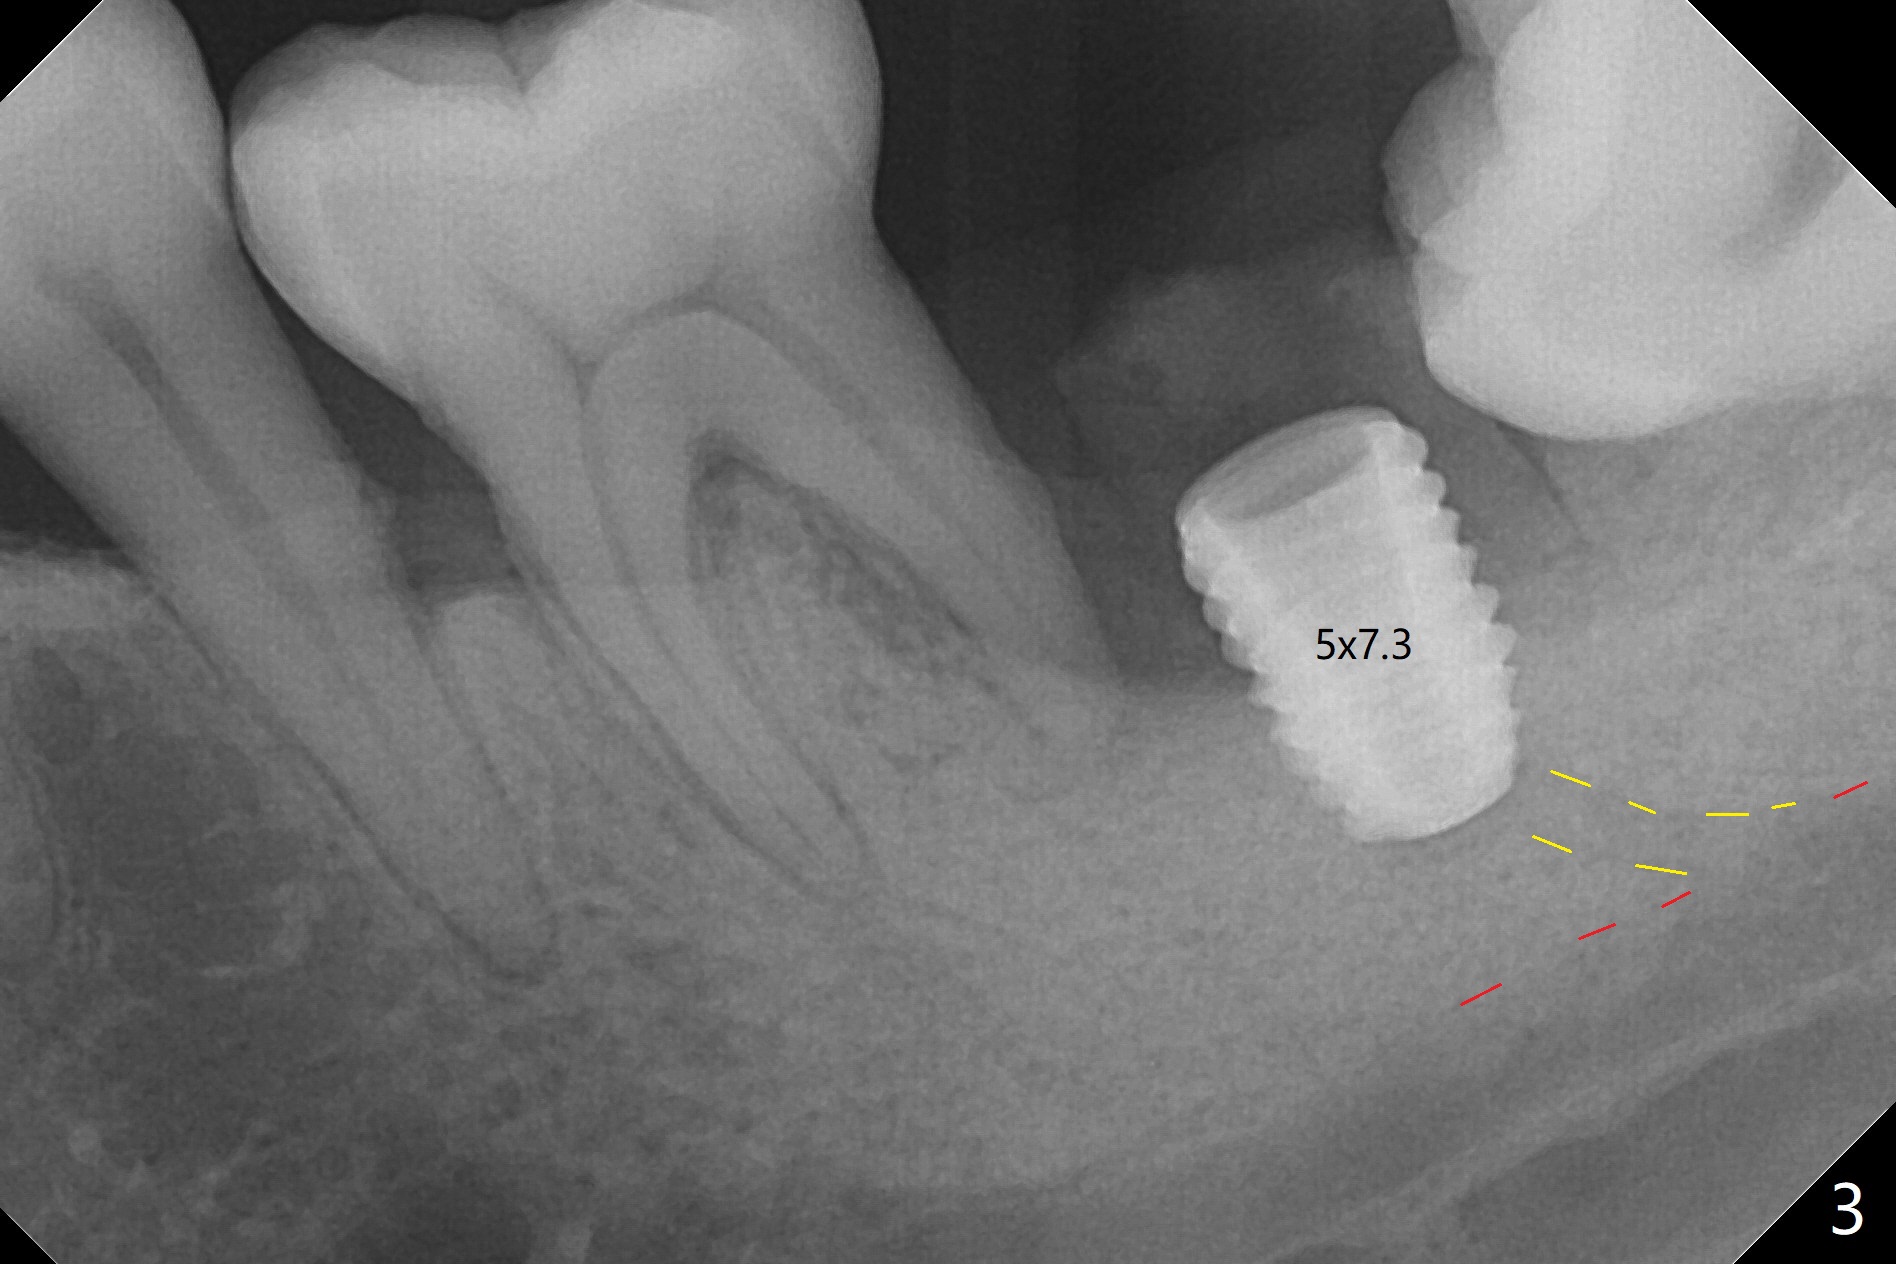

Socket shield (partial extraction therapies) is going to be conducted in this case to form a substitute buccal plate of the 2nd molar (Fig.1 *). The apex of the shield that contacts the 4.5x10 mm dummy implant cannot be removed because of poor access (Fig.2 * (12 mm offset)). Due to high bone density, a 4.5 mm drill has to be used in order to place a 5x7.3 mm definitive implant (Fig.3). In spite of the fact that the implant seems to be completely seated, the implant is ~ 1 mm supracrestal lingually. After implant removal, a 4.5x11.5 mm drill cannot reach the depth due to high bone density. 800 RPM instead of 50 RPM may help. When the implant is reseated, it appears to be .5 mm deeper than before clinically, although it looks incompletely seated in X-ray (Fig.4 <). The insertion torque is 60 Ncm. Allograft mixed with PRF is placed around the implant with cover screw, particularly mesiolinguodistal (Fig.4 *). The sockets of #17 and 18 are approximated with the help of 2 piece of PRF and collagen plug. The wound dehisces 9 days postop (Fig.5,6), although asymptomatic. Forced closure of the sockets with suture seems unnatural. An immediate provisional should have been fabricated. CT shows possible loss of part of bone graft (Fig.7). Regraft seems necessary in the appointment of uncover. Antibiotic is prescribed for another week. The gingiva seems healthy around the exposed healing screw 16 days postop (Fig.8). After debridement, the healing screw is then changed to a 4.5x5 mm healing abutment. The majority of the bone graft is lost without immediate provisional in 4 months (Fig.9 * (<: socket shield)). Then a 5.5x5 mm healing abutment is inserted for impression next appointment. A 5.2x4.5(4) mm cemented abutment is placed before impression (Fig.10). With socket shield (Fig.11 ^), the buccal gingiva looks more keratinized than the lingual one (Fig.12 *). Photos are taken immediately pre-cementation. Socket shield (*) covers the implant and abutment buccally (Fig.13 CT taken immediately pre-cementation).